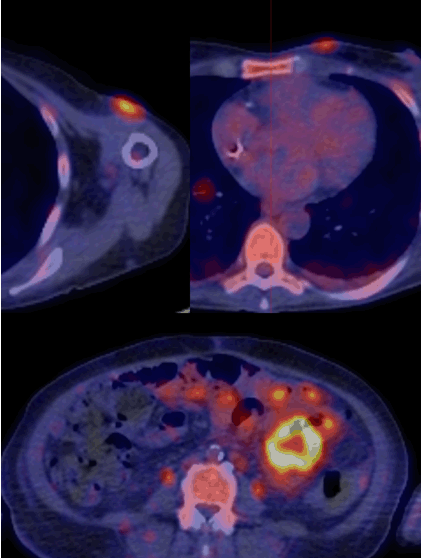

The PET scan showed intense FDG uptake in a left tonsillar mass with multiple FDG-avid subcutaneous lesions, and bowel and mesenteric involvement (Figure 1). The left tonsil and one of the cutaneous lesions were biopsied, revealing a CD8+ T-lymphoid cell infiltrate, most consistent with T cell lymphoma showing a CD4 negative, CD8 positive, and CD 56 negative cytotoxic phenotype. Balloon enteroscopy revealed a mosaiform small bowel mucosa with multiple clean-based ulcers throughout the jejunum. Biopsies were consistent with the tonsillar findings. A few days following admission the patient underwent a laparotomy for small bowel perforation, and was subsequently transferred to the intensive care unit where her course was complicated by recurrent gastrointestinal bleeding, septic shock and respiratory failure, leading to death.

Figure 1: 18-FDG PET scan showing multiple FDG-avid subcutaneous lesions as well as bowel and mesenteric involvement.